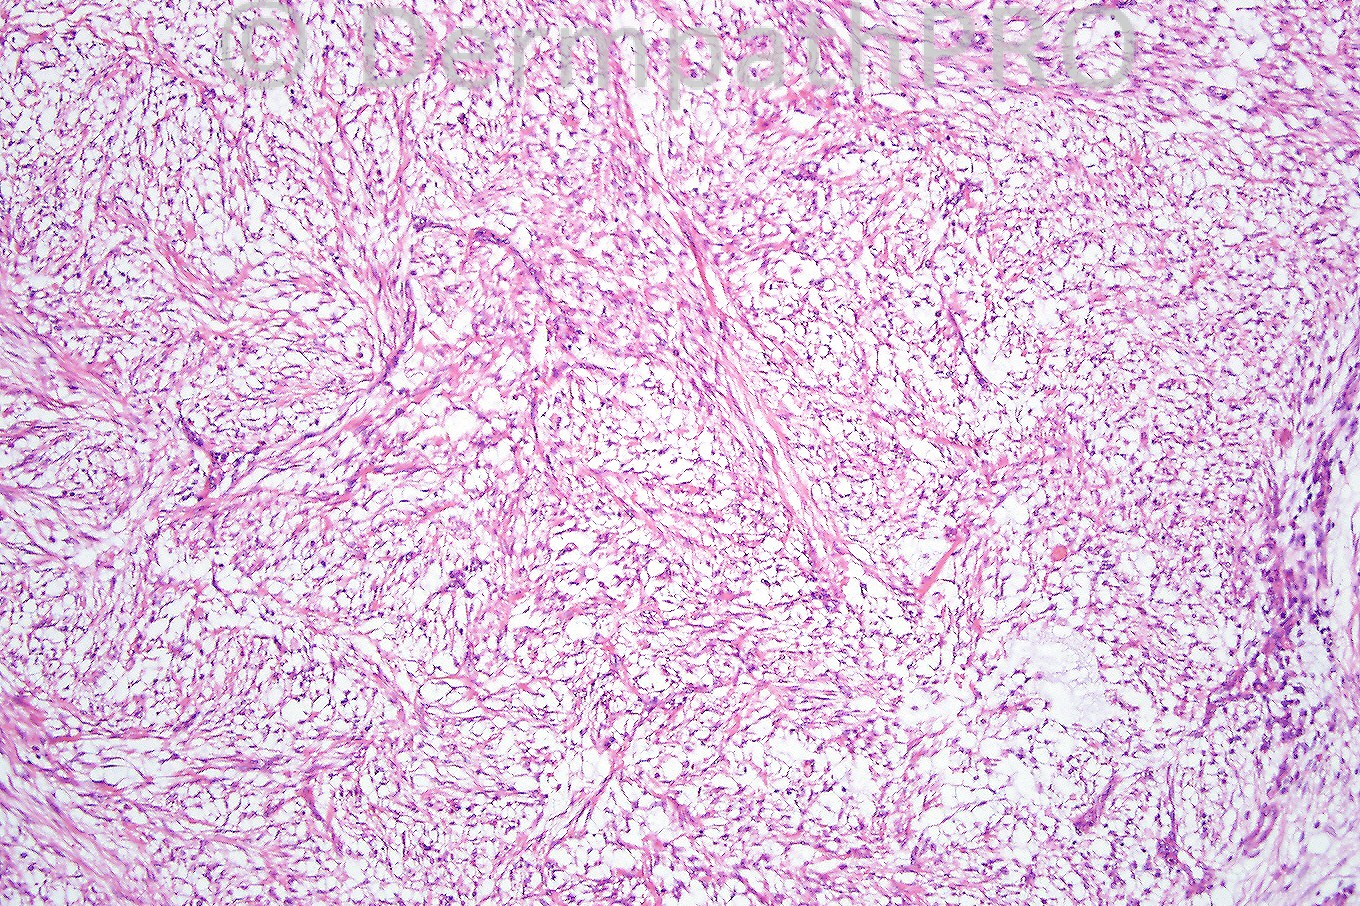

Male 2 years with a nodule on the scalp.